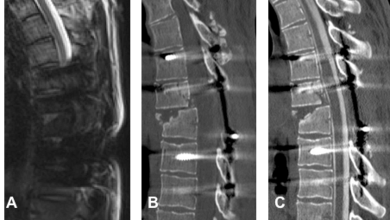

Die Myelographie ist ein invasives Verfahren an der Wirbelsäule. In der Neuroradiologie Heidelberg führen wir eine Myelographie jeweils nur zur weiterführenden bildgebenden Diagnostik bei Engen des Wirbelkanals oder der Nervenaustrittskanäle durch – also erst dann, wenn durch reguläre MRT- oder CT-Bildern nicht genaue Ergebnisse geliefert werden konnten. Vergleichen Sie hierzu unser gezeigtes Beispiel: